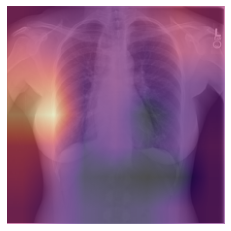

Class activation map (CAM)

CAM allows one to visualize which regions of the original image are heavily weighted in the prediction of the corresponding class. This technique provides a visualization of the activations in the final convolutional block of a Convolutional Neural Network (CNN).

CAM can also be useful to determine if the model is “cheating” and looking somewhere it shouldn’t be to make its prediction (i.e. radioopaque markers placed by the technologist).

Note: If you are running this cell in Colab, choose which of the two test images you would like to examine and run this cell to see the CAM output overlayed on the input image.

test_case = 'chest' #@param ['abd', 'chest']

cls = 0 if test_case == 'abd' else 1

label = test_case

y = get_image_files(path/'test'/label)

test_dl = learn.dls.test_dl(y, with_labels=True)

hook = hook_output(learn.model[0])

x, _ = first(test_dl)

with torch.no_grad(): output = learn.model.eval()(x)

act = hook.stored[0]

cam_map = torch.einsum('ck,kij->cij', learn.model[1][-1].weight, act)

x_dec = TensorImage(dls.train.decode((x,))[0][0])

_, ax = plt.subplots()

x_dec.show(ctx=ax)

ax.imshow(cam_map[cls].detach().cpu(), alpha=0.6, extent=(0,224,224,0),

interpolation='bilinear', cmap='magma');

hook.remove()